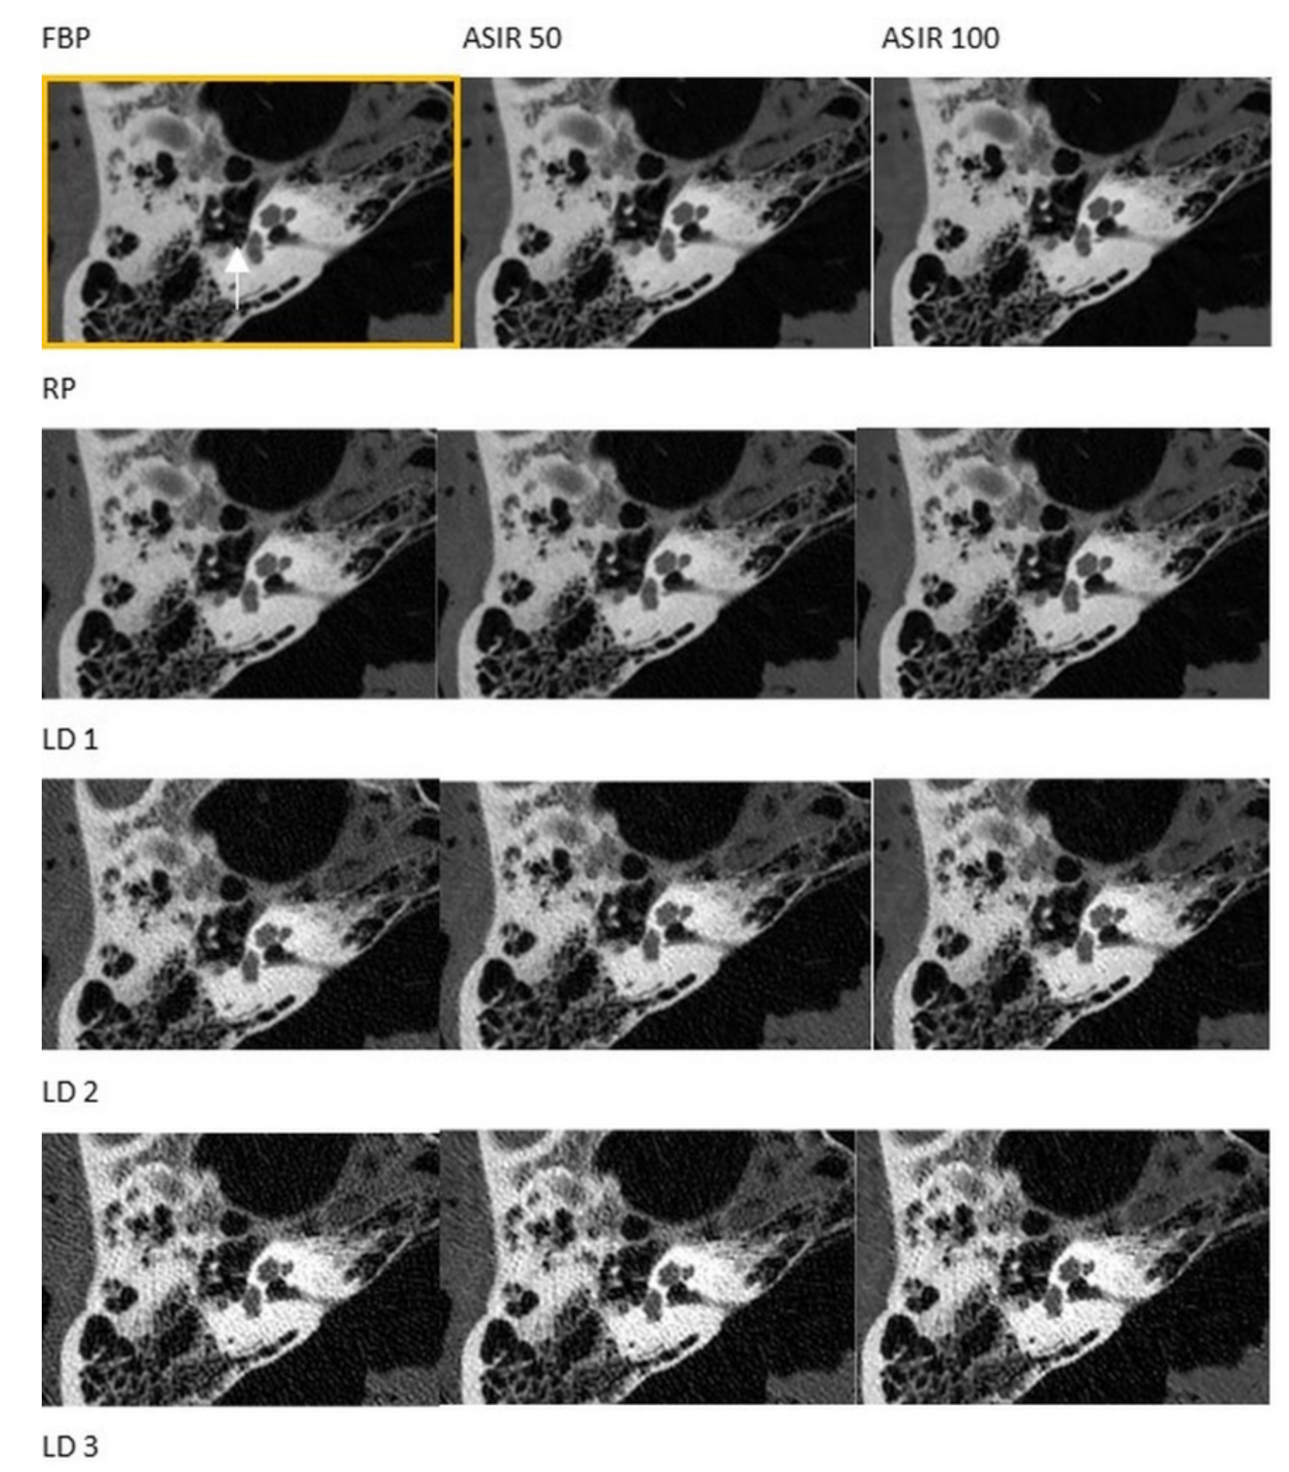

3.1. CT

3.2. CBCT